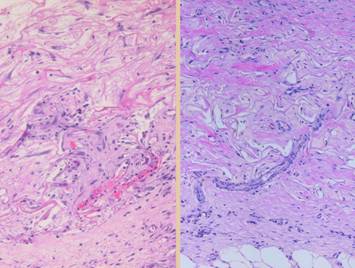

Left, a microscope image of normal wound healing.  The structure shown here is the prototypical wound.  Details of the structure and process will be explained in following panels.  Right, the microscopic appearance of fully regenerated Integra-CG matrix, the details likewise to be explained in following panels.  Even without explaining or focusing on specific details, the dissimilarity of the two can be appreciated.  Angiocytes and fibroblasts, vessels and connectives – that is all there is to these two tissues.  However, by supplying different “rules” or “subroutines” for the interaction and assembly of these elements, two different biomaterials emerge.  The rules or routines are based on the circumstances, reaction-to-injury versus embryonic regeneration.  The results have very different physical properties and implications for daily life, functional adaptations, and potential need for ongoing medical care.

Pictured is matrix regeneration within a piece of Integra collagen-gag matrix.  It is no longer the non-living empty matrix placed on the original wound, but a fully restored living material.  The details of this process are now presented.  However, even without knowing the specific details, it can be appreciated that the structure, morphology, and patterns of this regenerated biological material are different than the microscopic structure of the normal post-inflammatory wound.  Normal wound healing is triggered by inflammation and then evolves according to its own “program” of how angiocytes and fibroblasts rebuild a stroma of blood vessels and connective mesh.  Integra suppresses inflammation, and thus the normal “wound healing program” is never turned on.  Integra “heals” by a fundamentally different mechanism analogous to embryonic tissue generation.  Its build to a state of complete regeneration is uniform throughout the matrix, distributed rather than stratified, and when complete, it has created a new material that has characteristics mostly like normal dermis and quite unlike scar.  The matrix coaxes the same two cells, angiocytes and fibroblasts, to make a new tissue of blood vessels and connective mesh in a patterned morphology that is profoundly different then scar.  The same cells, making the same elemental components, assemble them in a completely different pattern than wound healing and scar because the embryogenesis-and-stromal-generation “program” is entirely different than the healing-and-scar “program”.